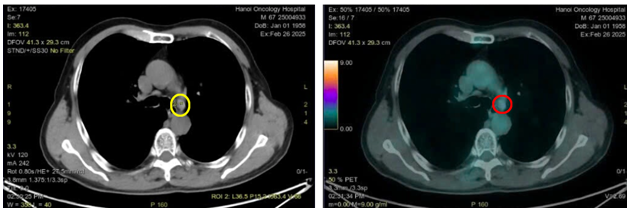

Hình 1: Hình ảnh nốt đặc thùy dưới phổi trái kích thước 10x14mm trên của sổ nhu mô (vòng tròn màu vàng) và cửa sổ trung thất (vòng tròn màu đỏ)

Hình 4: Hình ảnh tổn thương u phổi thùy dưới phổi trái kích thước 10x15mm trên CT (vòng tròn màu vàng) và PET/CT (vòng tròn màu đỏ) tăng chuyển hóa FDG (SUVmax: 9,8)